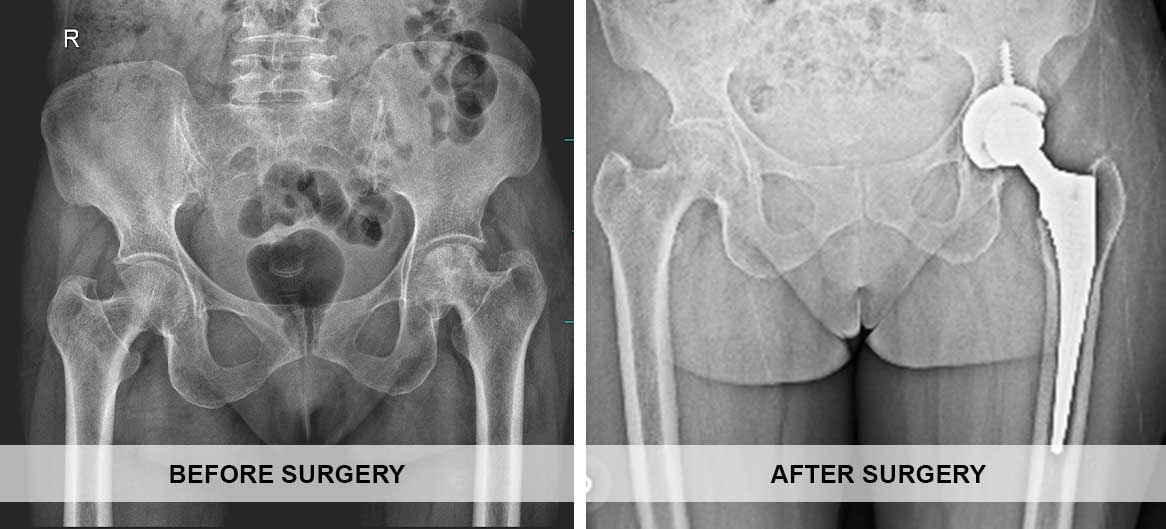

Total Hip Replacement